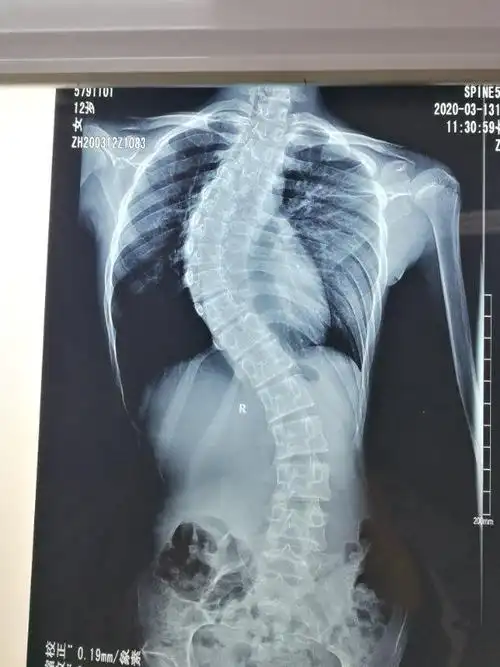

12岁女孩脊柱侧弯曲超过60度,手术矫正后"长高"4厘米